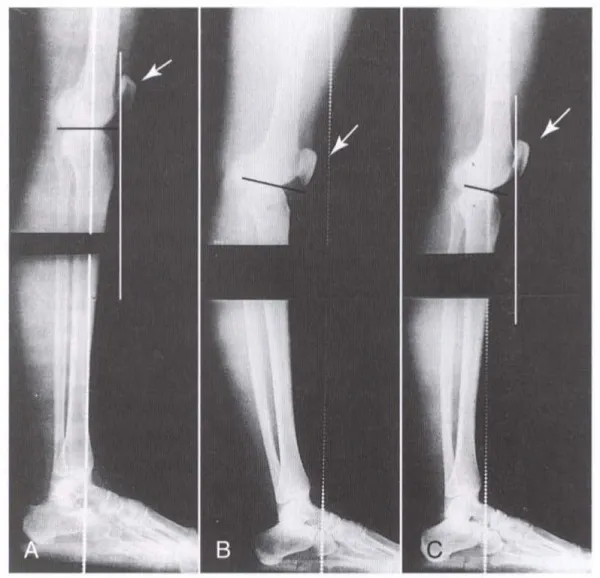

Ví dụ về trường hợp trong ảnh, hình A là đầu gối của người bình thường, hình B là đầu gối của người đứng thường xuyên trụ 1 chân, trong tư thế Hyperextend (bẻ ngược khớp ra sau). Như bạn có thể thấy vào trường hợp B, xương cẳng chân đã bị đẩy dịch ra phía sau so với xương đùi. Và ngay cả khi được điều chỉnh về tư thế bình thường (hình C) thì xương chày vẫn nằm tụt về đằng sau. Chưa kể đến thay đổi trên bề mặt xương trong quá trình chịu lực lâu ngày.

Bởi vậy để correct được cho một người không phải chuyện đơn giản và cũng không phải lúc nào cũng may mắn có thể khắc phục được. Đôi khi chỉnh sửa xong ta lại không 1 kết quả tồi tệ hơn. Bởi vậy lời khuyên của Phương là hãy chỉ tác động đến những trường hợp gặp vấn đề với cơ bắp mà thôi. Nếu như bạn không đủ kĩ năng (mà đa phần là thế) thì hãy tư vấn kêu kiếm người có chuyên môn, đừng cố làm việc ngoài khả năng của mình.